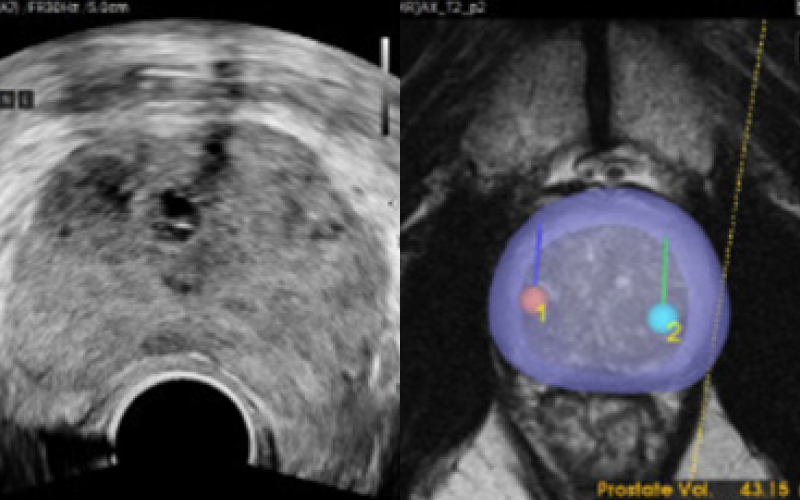

MR 퓨전 조직검사가 주목받는 이유.

최첨단 AI와 3D 융합 영상으로 진단 정확도를 혁신적으로 높인 골드만만의 특별한 조직검사입니다.

기존 검사는 병변 유무와 관계없이 12군데를 무작위로 채취해 정확도가 낮고 재검 가능성이 높았습니다. 하지만 MR 퓨전 조직검사는 병변을 직접 겨냥해 조직을 채취하므로 진단율이 크게 향상되었습니다.